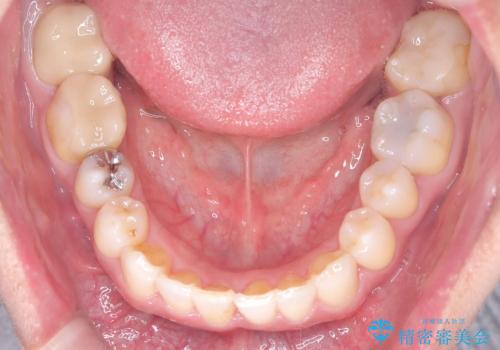

- 「八重歯と歯のでこぼこを治したい」を主訴に来院された患者様です。

歯は抜かずに奥歯の遠心移動とIPRで八重歯とでこぼこを改善しました。

左上3番は保険治療(CR)の劣化による二次カリエスになっていますので、後日治療予定です。